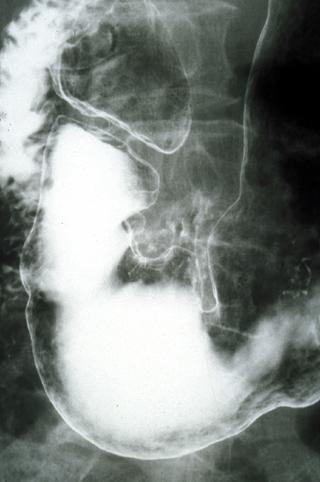

Criteria of Hist.ClassificationMalignant epithelial tumor/Adenocarcinoma

LocationStomach/Antrum

Technique, MethodX-ray

Macroscopic TypesType 0/IIa (IIa+IIc) Superficial elevated and depressed type

Size20 - 24

Depth of Tumor Invasionsubmucosa